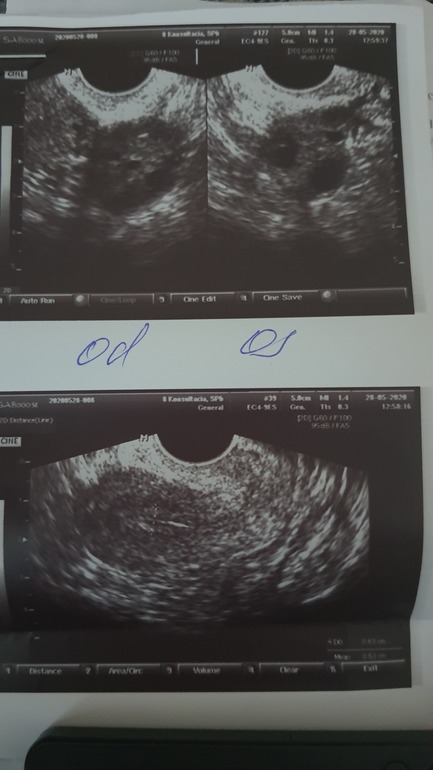

В итоге месячных нет. Единственное были выделения розовые, вот как перед мес бывают. И начались они именно в тот день когда должны были придти месячные. И длились они ровно столько сколько месяч идут. 4 дня. В итоге Получается Задержка 3 недели. 25.05.2020 СДАЛА ХГЧ -0.01🤷♀️🤷♀️ 28.05.2020 Сделала узи-все как всегда без изменений. Беременности нет. Врач сказал для нового и старого цикла значения не понятные..